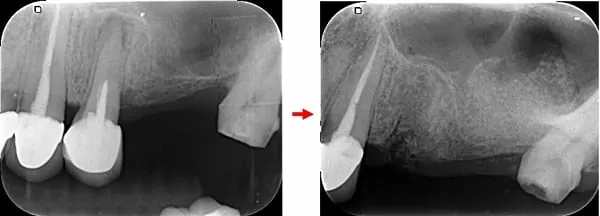

治療前:左上後牙區鼻竇太低、骨量不足 → 治療後:微創補骨增高鼻竇,不腫脹

照射X光片及3D斷層掃描後,確認左上因為缺牙太久,鼻竇氣室化導致骨質流失,幾乎沒有骨頭可以植牙;必須先補骨做鼻竇增高,等待新骨生成後才能植牙。傳統的鼻竇增高手術是一個大手術,通常用側方開窗法施行,患者術後會疼痛而且臉會非常腫脹,非常不舒服。現在科技的進步,已經能用微創法補骨,不僅更安全,而且患者不會腫脹而且低疼痛,讓很多以前不敢做這項手術的人,現在都敢做了!

治療前:第一小臼齒發炎導致外側骨破洞 → 治療後:拔除後窩洞填入骨粉及膠原蛋白

治療前:鼻竇非常低 → 治療後:墊高鼻竇,填入大量骨粉